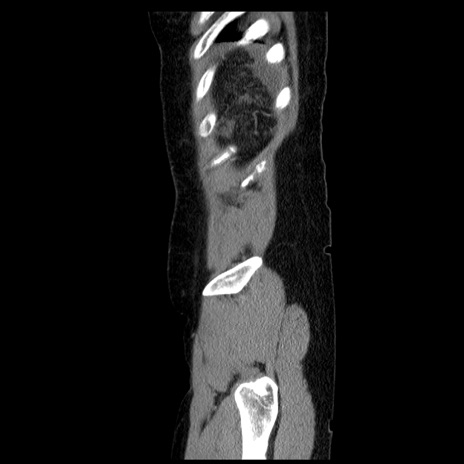

症例6(矢状断像)